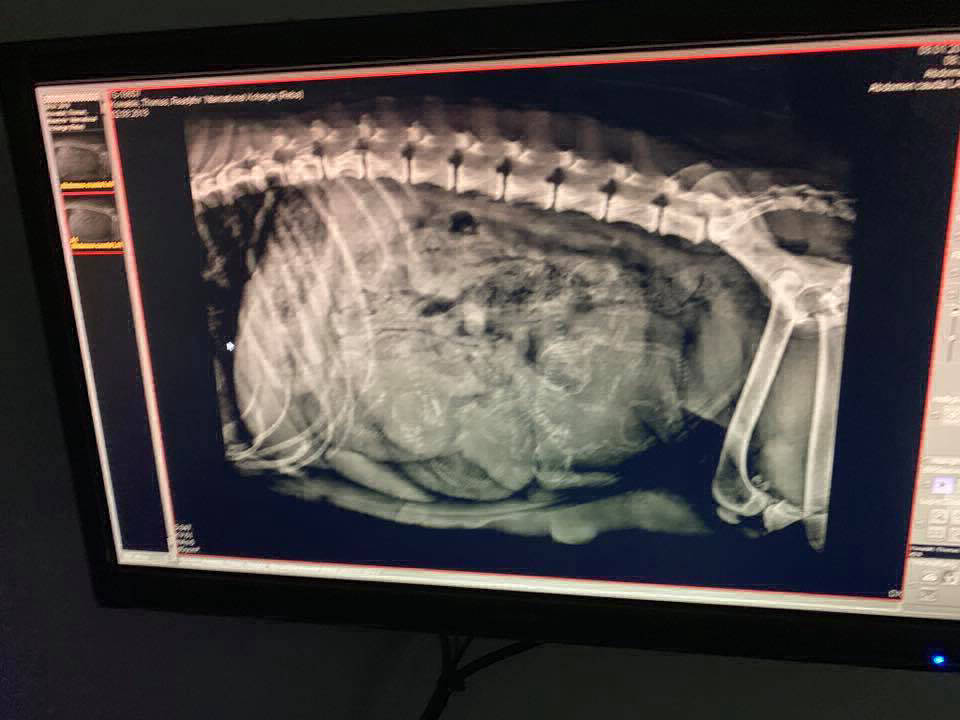

Hündin: "Reba" Readyfor `Nternational Xchang

19.01.2019

heute hat Reba 6 gesunde Welpen (3m/3w) zur Welt gebracht